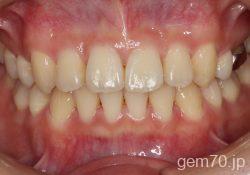

主訴)前歯のかみ合わせが深い

診断)過蓋咬合

年齢)21歳

使用装置)マルチブラケット装置(セラミックブラケット)

治療方法)4|4/4|4

治療期間) 2年8ヵ月 通院回数 32回